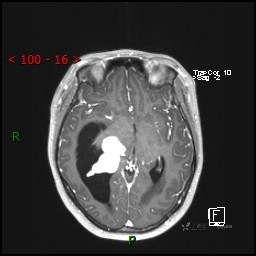

辅助检查:CT MRI

临床诊断:脑室占位

CE